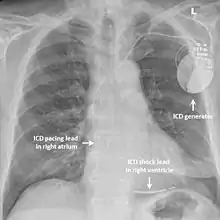

Implantable cardioverter-defibrillator

While medication and sympathectomy aim to prevent abnormal heart rhythms from occurring in the first place, an implantable defibrillator (ICD) may be used to treat arrhythmias that medication has failed to prevent and restore a normal heart rhythm.[2] These devices, usually implanted under the skin at the front of the chest below the shoulder, can continuously monitor the heart for abnormal heart rhythms. If a life-threatening arrhythmia is detected, the device can deliver a small electric shock to terminate the abnormal rhythm and restart the heart.[1]

Implantable defibrillators are often recommended for those with CPVT who have experienced blackouts, ventricular arrhythmias or cardiac arrest despite taking appropriate medication.[2] These devices are life-saving, as it has been shown that their use confers a significant survival benefit in patients with CPVT.[25] It has been suggested that the resulting surge of adrenaline caused by the pain of an electric shock from the device could theoretically bring on a cycle of recurrent arrhythmias and shocks known as an electrical storm,[4] and therefore it is strongly recommended that those with an ICD implanted for CPVT take a beta blocker to dampen the effects of adrenaline.[4]